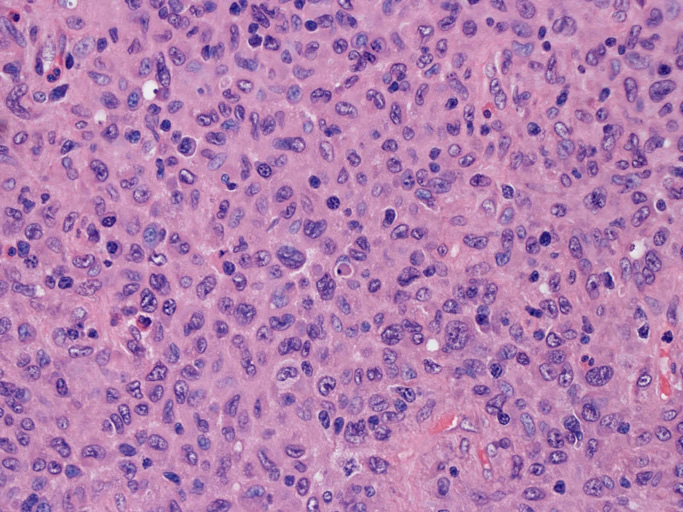

大型細胞の増殖よりなる腫瘍。縦溝,しわ,切れ込みのある核をもった大型細胞も出現する。クロマチンは顆粒状で核小体も明瞭である。核分裂は >50/10hpfと多い。eosinophilsは少ない。壊死が多発することがある。未分化ないし低分化な細胞像, 組織所見のため鑑別診断は多岐にわたり、的確な免疫染色を行う必要がある。

皮膚に異型細胞の浸潤がみられる。異型細胞は表皮内に浸潤するほか、表皮真皮境界部, 真皮, 皮下脂肪組織にもびまん, 結節様の浸潤所見を示す。血管周囲に浸潤、集蔟する所見も多く見られる。 増殖浸潤細胞の核には類円形や腎臓形, またはへこみ, 切れ込み, 溝などを有する多型な核が認められる。クロマチンは粗でvesicularな核が多い。核小体の明らかな核もある。好エオジン性の核内封入体様構造も少数に見られた。mitosisは容易に認められる。hyperchromaticな多型核, bizzarreな細胞が高頻度に認められ異型度は高いと考えられる。細胞質は境界不明瞭, 淡明または泡沫様の 好エオジン性胞体である。

免疫染色 浸潤細胞はCD1a+, S100+, Langerin+, HLA-DR+, CD4+, CD45+, CD68+. MIB-1 index:24.4%

Speaker's Pathological Diagnosis: Langerhans cell sarcoma, skin, rt. knee, biopsy